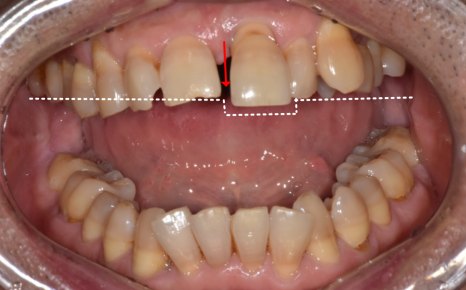

왼쪽 앞니가 아래로 더 내려앉는 느낌

찬 것만 먹어도 시린 증상

앞니 사이 틈이 점점 넓어지는 변화

시간이 지날수록 위의 증상이 심해져서 고민하고 계셨습니다.

입안을 확인했을 때,

해당 부위 잇몸 안쪽으로 치석이 보였습니다.

230413 잇몸 내려감으로 길어진 치아, 방치하면 안 되는 원인, 증상, 이유